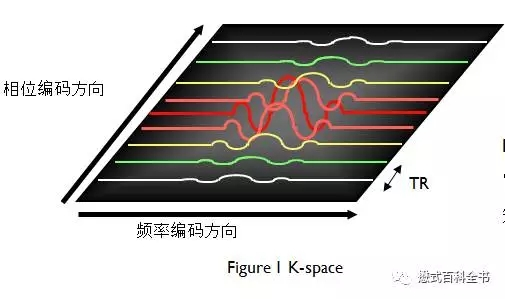

上图是一个K空间的示意图,我们知道磁共振需要需要对质子进行空间定位,会用到不同方向的梯度磁场。

如果以一个2D采集为例,首先通过层面选择梯度,激发某一固定的一层,然后在通过相位偏码梯度和频率编码梯度来对该层的质子进行空间定位。

一个二维平面,我们可以把它分为两个正交方向,即:Ky(相位编码方向)和Kx(频率编码方向)。一个TR周期,把采集的一次信号填充到K空间中,在相位编码方向上,有多少个步级,我们就需要填充多少个相位编码线,最后把K空间数据填充完毕,进行图像后处理形成磁共振图像。

图4:频率编码梯度在采集接收信号的时候持续地施加,信号采样持续时间为Ts(图中为TO),频率编码梯度也持续到该过程结束。

在MR图像采集过程中,每填充一条相位编码线,相位编码梯度都发生变化,而频率编码梯度并不变。

相位编码梯度变化一次,进行质子的相位编码方向(Ky)的定位。在频率编码方向上,一次信号采集,会采集很多的采样点,作为频率编码方向(Kx)的定位。